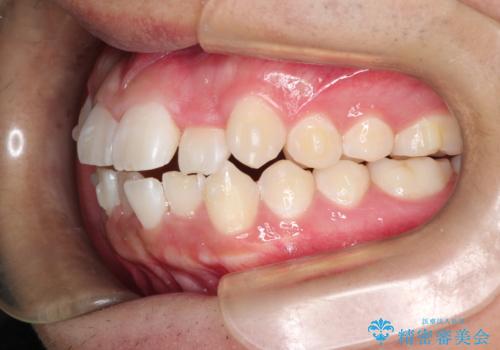

- 前歯のがたつきを主訴に来院されました。

上顎の前から2番目の歯の噛み合わせが反対になっていました。

抜歯矯正も考えられるケースでしたが、非抜歯での矯正を希望され、インビザラインにて治療することとなりました。

目立たずに矯正を終えることができ、患者様にも満足していただきました。